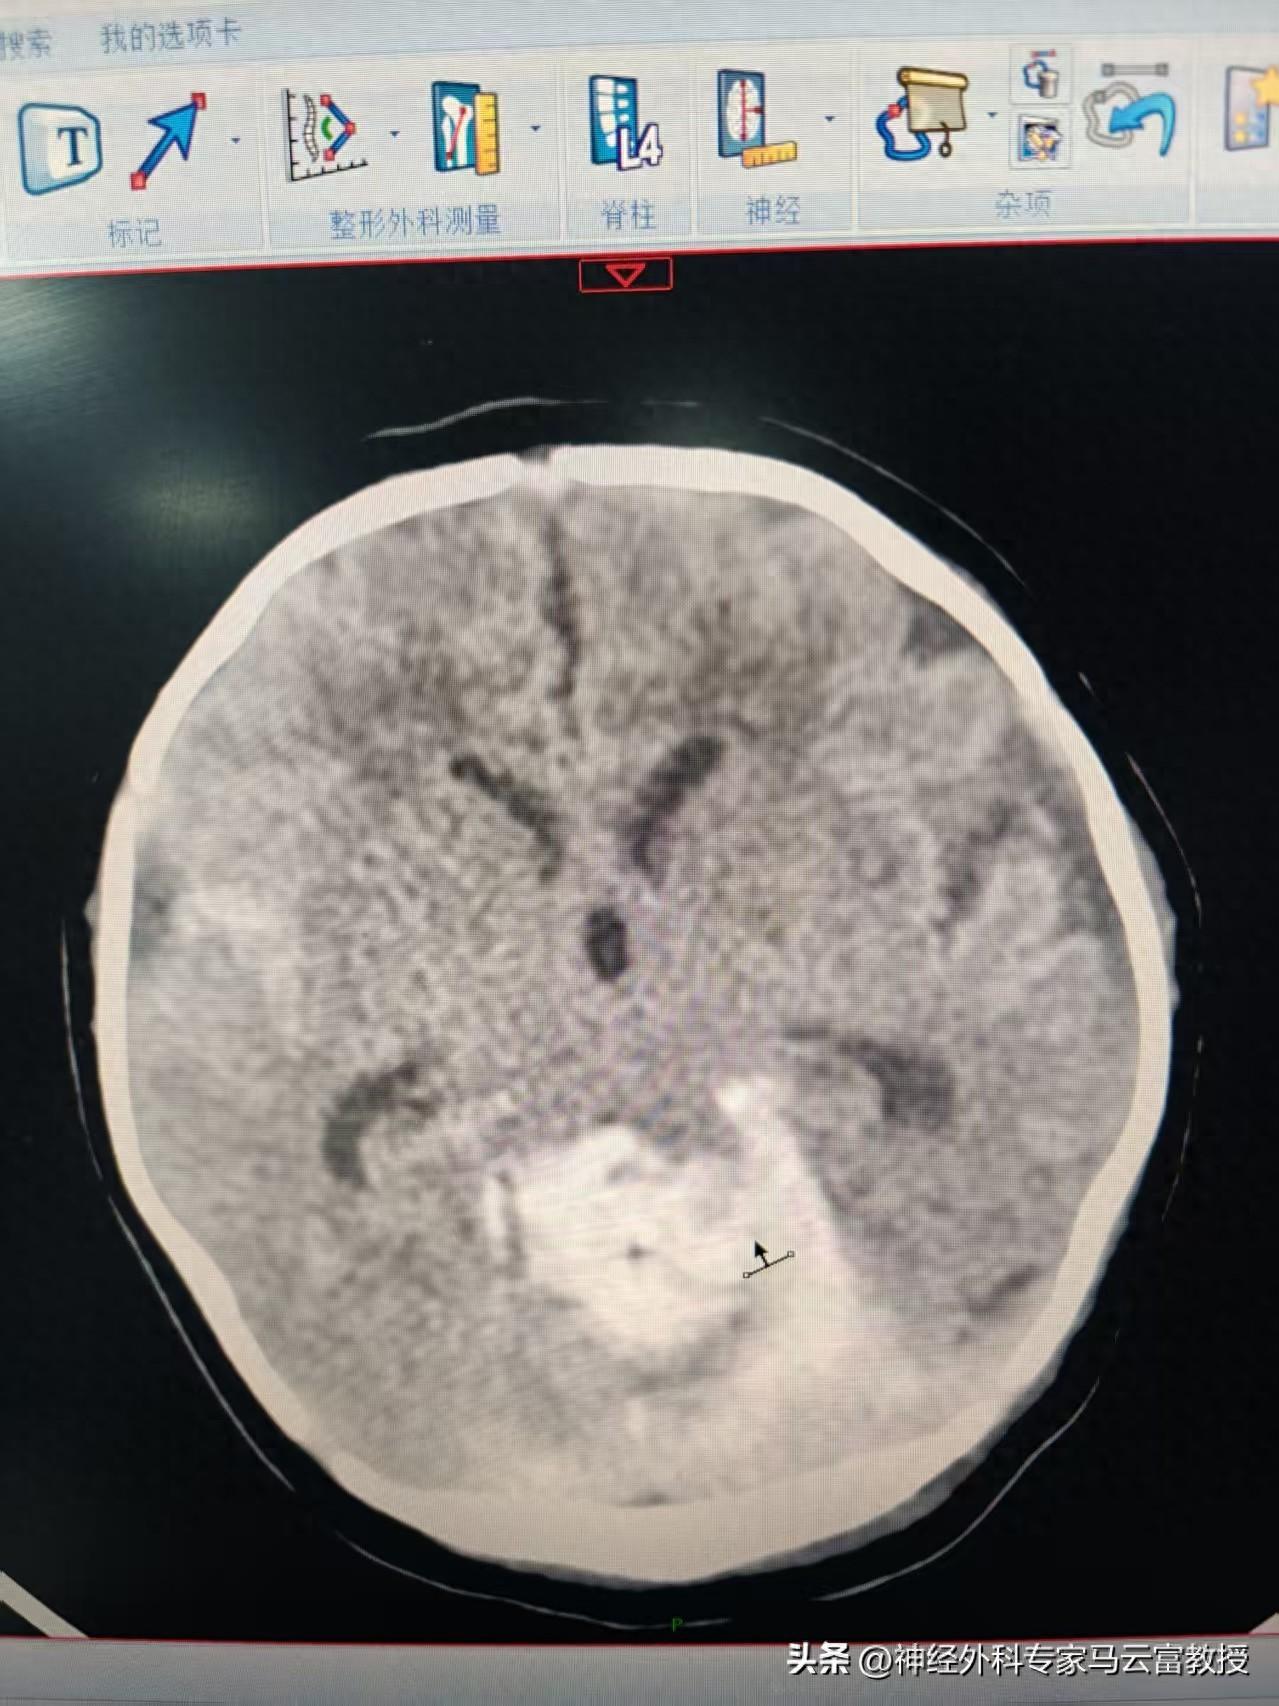

新生兒顱腦CT顯示腦出血

這是一個稚嫩的小生命,還沒來得及好好看看這個世界,就被病痛籠罩。檢查顯示,寶寶小腦出血範圍大,血腫壓迫嚴重,隨時可能危及生命。值班醫生迅速趕到新生兒科查看患兒,同時第一時間將情況彙報給馬雲富主任和夏星副主任。